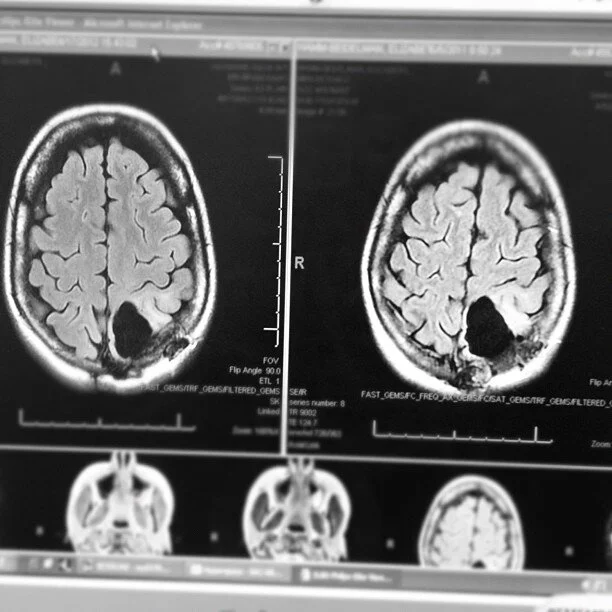

MRI one-year post Temodar chemotherapy

Photos: My brain as of May 21, 2009